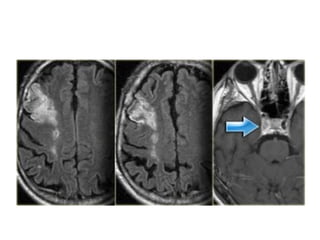

• On T2WI and FLAIR infarction is seen as

high SI.

These sequences detect 80% of

MRI VS TIME

• In the acute phase T2WI will be normal,

but in time the infarcted area will become

hyperintense.

• The hyperintensity on T2WI reaches its

maximum between 7 and 30 days. After

this it starts to fade

• DWI is already positive in the acute phase

and then becomes more bright with a

maximum at 7 days.

• DWI in brain infarction will be positive for

approximately for 3 weeks after onset (in

spinal cord infarction DWI is only positive

for one week!).

• ADC will be of low signal intensity with a

maximum at 24 hours and then will

increase in signal intensity and finally

becomes bright in the chronic stage.